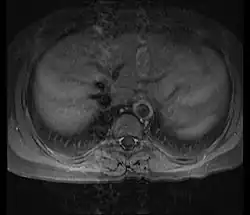

Axial T1-weighted post-gadolinium MRI in a patient with Takayasu arteritis showing thickened, enhancing aortic wall, consistent with large vessel vasculitis

Although the exact cause of Takayasu arteritis is unknown, the condition is marked by segmental and patchy granulomatous inflammation of the aorta and its major branches. This inflammation can lead to narrowing of the arteries (stenosis), blood clots (thrombosis), and the formation of aneurysms.[5]

Chronic inflammation often results in irregular fibrosis of the vessel wall, particularly affecting the innermost layer, which may become significantly thickened.[7] These changes -- including narrowing due to inflammation, granuloma, and fibrosis -- are commonly observed through imaging techniques such as magnetic resonance angiography (MRA), computed tomography angiography (CTA), or arterial angiography (DSA).